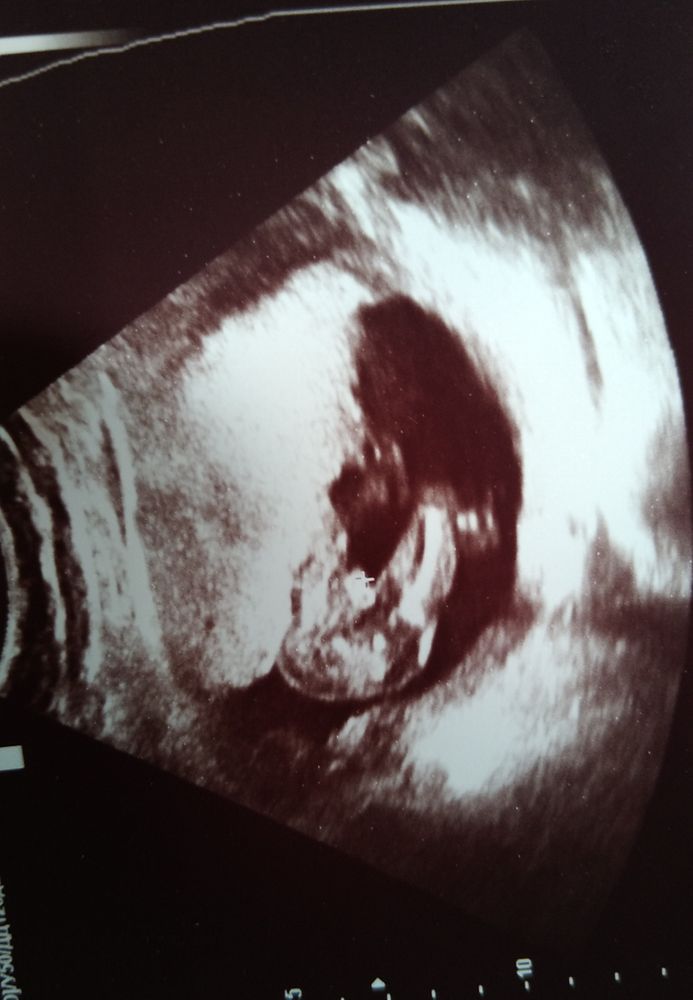

Сегодня сходила на УЗИ по поводу тянущей боли в животе. Слава Богу с малышом всё хорошо, не большой тонус только, а как бонус посмотрели пол... Папа наш счастлив. А я не представляю как быть

Девочки подскажите пожалуйста. Вчера была на УЗИ ДШМ 31 мм, узист ничего не сказала, меня осенило только дома. Естественно горе от ума полезла в интернет.... и много кто пишет что накладывали швы, написала врачу своему, она мне говорит это норм. А мне видать только повод для переживаний дай. Но я теперь себе д

Девочки, подскажите пожалуйста. ранее писала, что в гос ПЦ из за миомы скрининг перенесли на неделю, и я для себя пошла в Гемотест. По узи КТР 58 мм, ЧСС 168, носик есть), ТВП 1,1 и пришла кр